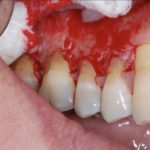

Стоматологи выделяют три степени протекания болезни. На первой и самой легкой стадии образуется карман в десне глубиной до 4 мм. Пока ощущения неприятные, но терпимые. Изменения в костной ткани еще не начались. Средняя степень тяжести характеризуется увеличением глубины кармана до 6 мм. Такой периодонтит симптомы имеет более явные: корни зубов слегка оголяются, десны воспалены, зубы становятся подвижными. Тяжелая стадия – это карман глубиной уже до 9 мм, сильное нагноение. Зубы меняют свое положение, а их подвижность настолько сильная, что не позволяет нормально питаться.

Во время сильного воспаления сначала освобождают каналы от содержимого. Для этого применяют дренаж через десну, корневые каналы или лунку, если зуб был удален. Если апикальный периодонтит локализован глубже, разрезают переходную складку. Обычно этот метод применяется при абсцессе, которое является одним из осложнений заболевания. Все манипуляции осуществляют под местным обезболиванием, чтобы добраться до пораженного участка без причинения дискомфорта пациенту.